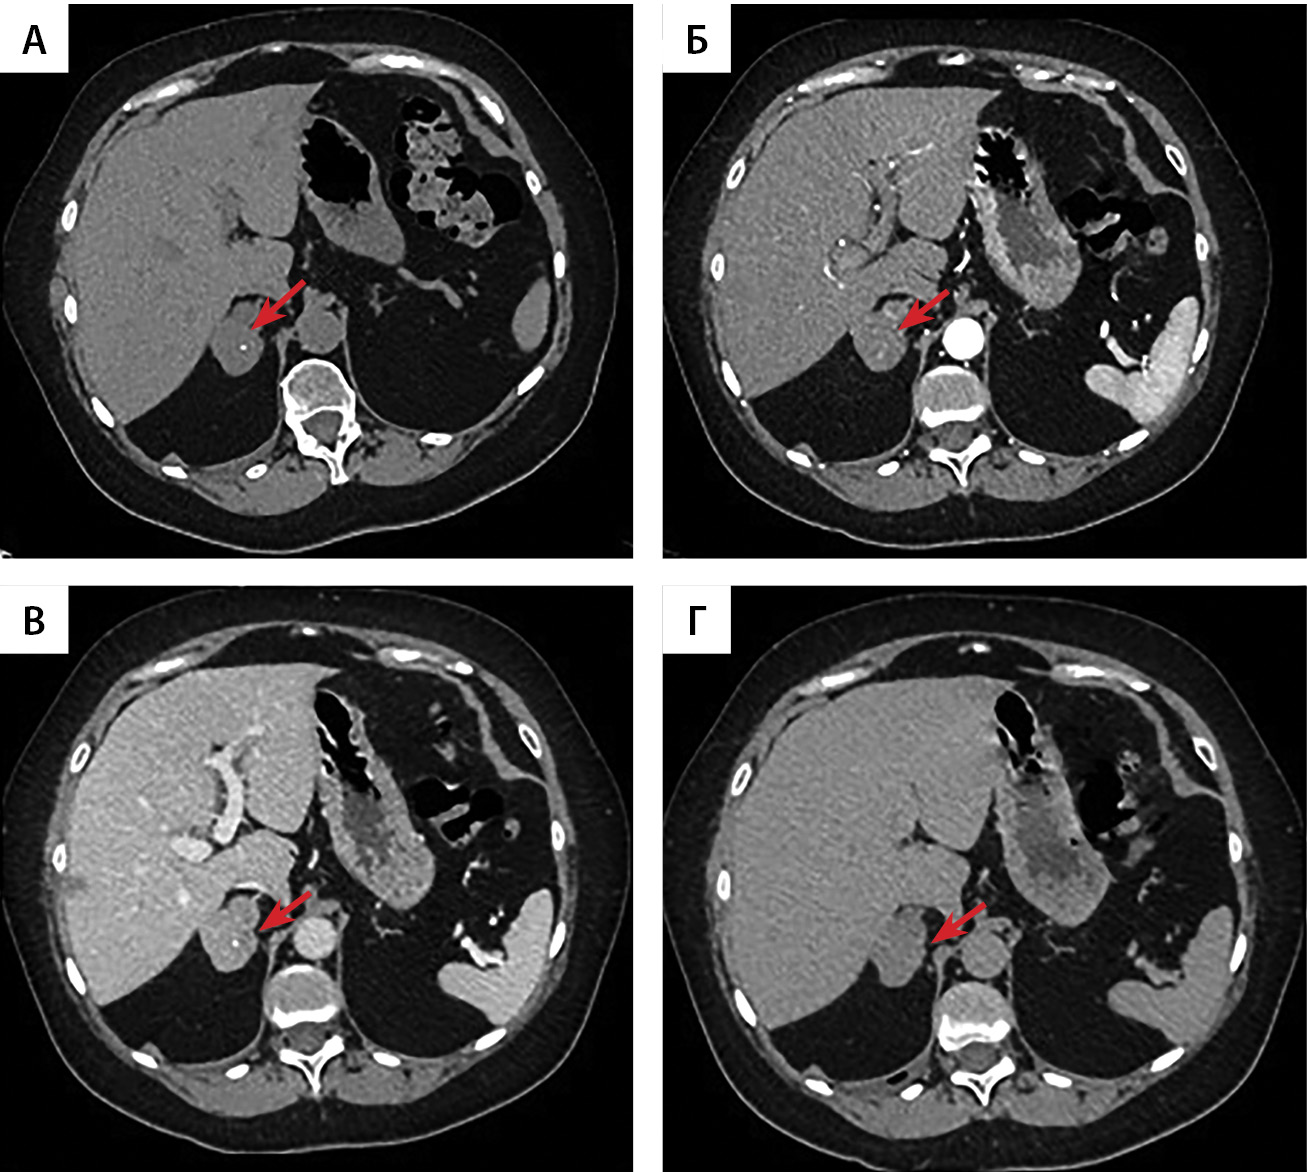

По данным мультиспиральной компьютерной томографии (МСКТ) надпочечников: образование левого надпочечника бобовидной формы с четкими ровными контурами, однородной структуры, размерами 25×14×20 мм. При болюсном контрастном усилении образование неоднородно накапливает контрастный препарат, максимально в венозную фазу. Плотность его по фазам составляет (нативная-артериальная-портальная-отсроченная): 50–59–106–54 ед.Н. Вымывание контрастного препарата: абсолютное 92,9%, относительное — 49,1%. Регионарные лимфатические узлы не увеличены. Образование правого надпочечника овальной формы с четкими бугристыми контурами, неоднородной структуры, размерами 29×41×35 мм. В структуре определяются кальцинаты. При болюсном контрастном усилении образование неоднородно накапливает контрастный препарат, максимально в венозную фазу. Плотность по фазам составляет (нативная-артериальная-портальная-отсроченная): 46–55–104–52 ед.Н. Вымывание контрастного препарата: абсолютное 89,7%, относительное — 50%. В артериальную фазу в структуре обоих образований определяются мелкие гиперконтрастные включения плотностью до 188 ед.Н. Регионарные лимфатические узлы не увеличены (рис. 1, 2, 3). По заключению — образования обоих надпочечников необходимо дифференцировать между атипичными аденомами с низким содержанием жира и образованиями злокачественной природы.

Рисунок 2. Мультиспиральная компьютерная томография образования правого надпочечника, аксиальная проекция: А — нативная фаза; Б — артериальная фаза; В — портальная фаза; Г — отсроченная фаза.

4. Рисунок 2. Мультиспиральная компьютерная томография образования правого надпочечника, аксиальная проекция: А — нативная фаза; Б — артериальная фаза; В — портальная фаза; Г — отсроченная фаза. | |